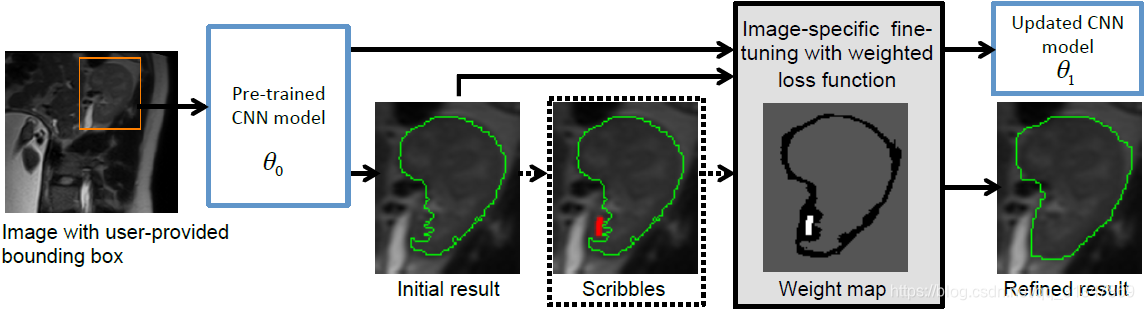

测试过程:

测试时,由用户提供一个 bbox,输入训练好的 CNN 模型中(参数为

θ

0

\theta_0

θ0)可以得到一个初始的分割结果(Initial result),再由用户进行有监督的微调或无监督的微调(Scribbles),对初始的分割结果进行调整,得到一个更新后的 CNN 模型(参数为

θ

1

\theta_1

θ1,Refined result)

【在测试阶段需要用户提供 bounding box,但是也可以研究一下自动生成 bbox 来进一步提高效率】

在第一步训练好 CNN 模型参数 θ 0 \theta_0 θ0 以后,接着就在测试阶段对模型进行 fine-tuning,也就是更新参数 θ 0 \theta_0 θ0,最终要得到更新后的参数 θ 1 \theta_1 θ1。

在测试阶段,用户为测试图像提供一个 bounding box 然后输入到训练好的 CNN model ( θ 0 \theta_0 θ0 ) 中,CNN 根据 bbox 得出一个初步的分割结果 Y ^ 0 \hat Y_0 Y^0。

接着对分割结果 Y ^ 0 \hat Y_0 Y^0 进行有监督或无监督的 fine-tuning,即画一些修正的 scribbles,根据这些 scribbles 对结果再修改。